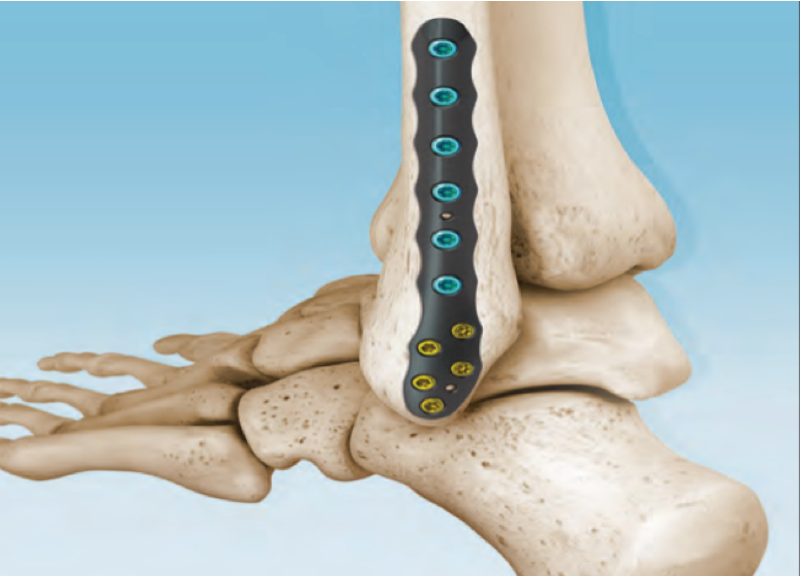

CONMED Foot and Ankle offers tailored innovation and simplified solutions. Explore our complete portfolio of arthroplasty, biologic, fixation, implant, suture anchor, and instrumentation offerings for foot and ankle surgery.